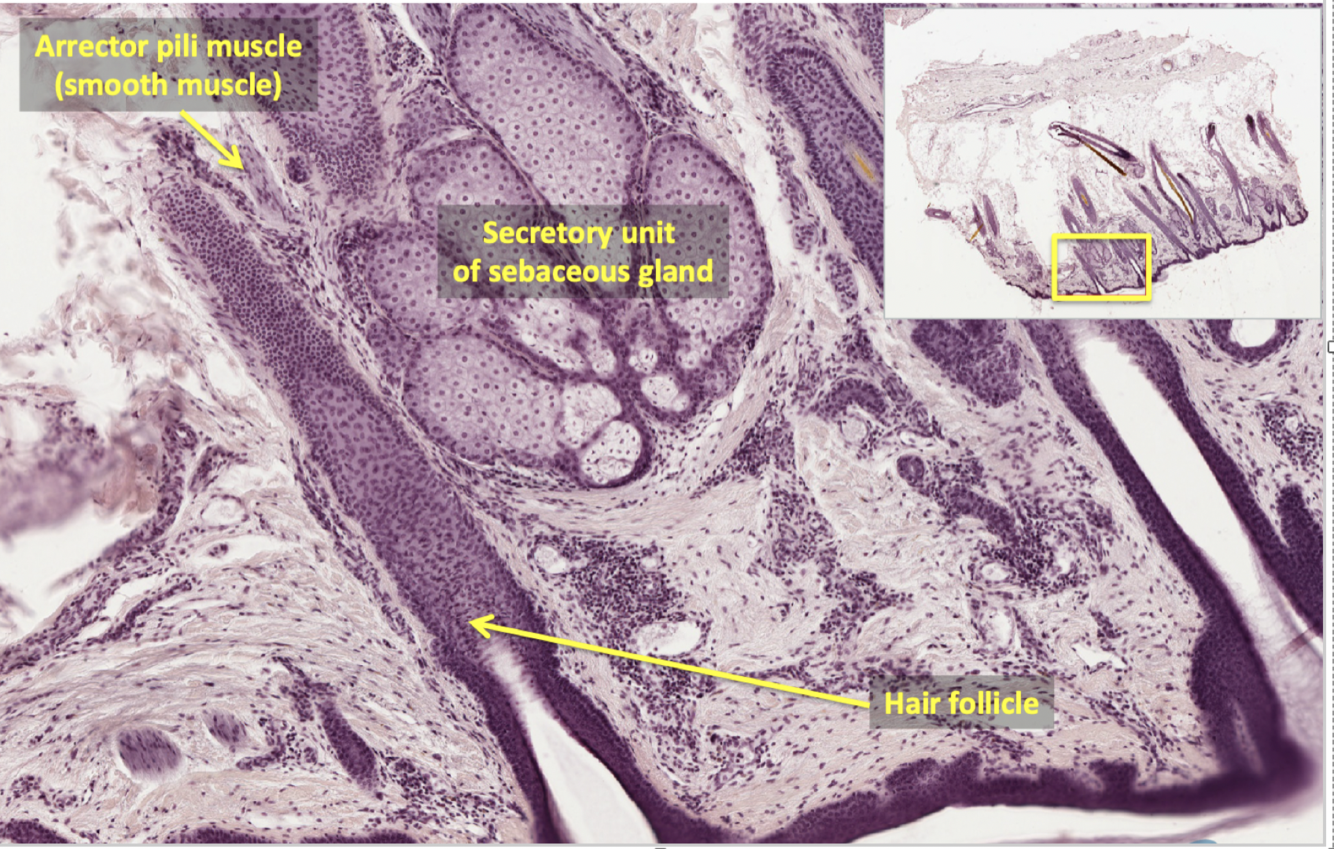

what type of muscle is arrector pili muscle